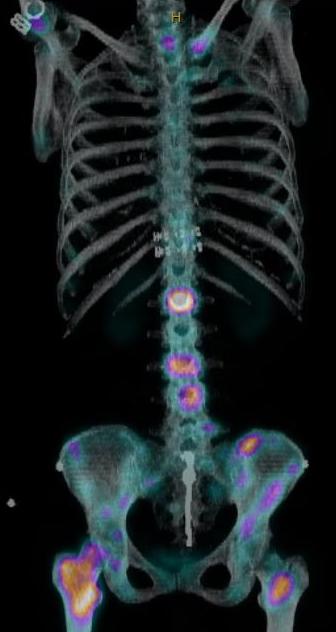

Bone scan / PET-CT

Polyostotic / monostotic

False negative 10% - Myeloma / Melanoma / Renal cell carcinoma

Multiple vertebral and rib metastasis bone scan PET scan breast cancer